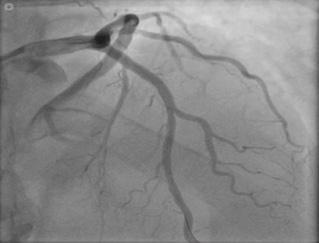

Coronariografía (angiografía coronaria)

Es una prueba invasiva y definitiva para valorar la gravedad de la enfermedad coronaria (gold estándar).

Se indica en casos de angina severa (grado III – IV), falta de respuesta al manejo médico, alto riesgo en pruebas funcionales o previo a la revascularización.